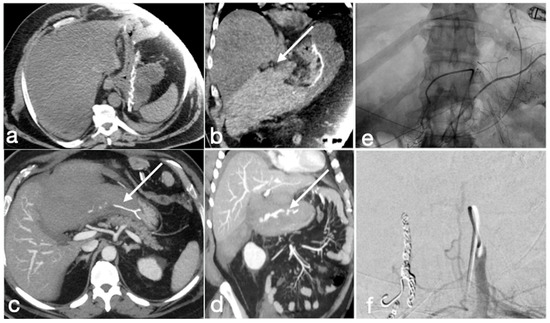

Figure 10. Gastric band slippage with gastric obstruction. A 40-year-old female with known gastric banding was complaining of abdominal pain and vomiting. There is dilatation of the esophagus (a, axial view, arrow) and of the gastric lumen proximal to the gastric banding (b, axial view, arrow). These findings are best seen in the coronal views (c,d, esophagus and stomach, straight arrows; gastric banding curved arrows). In (e) is shown the phi angle, excessively wide (134,699°), and in (f) the volume rendering reconstruction in which the excessive angulation of the device is clearly seen.